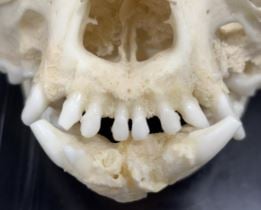

We planden voor Rosa een premaxillectomie in, waarbij we een resectie doen van beide os incisivi inclusief alle omgevende weke delen/structuren (en block excisie).